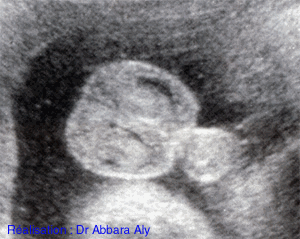

Sexe fœtal masculin :

Image échographique montrant l'aspect des organes génitaux

externes masculins chez un fœtus a 34 SA n